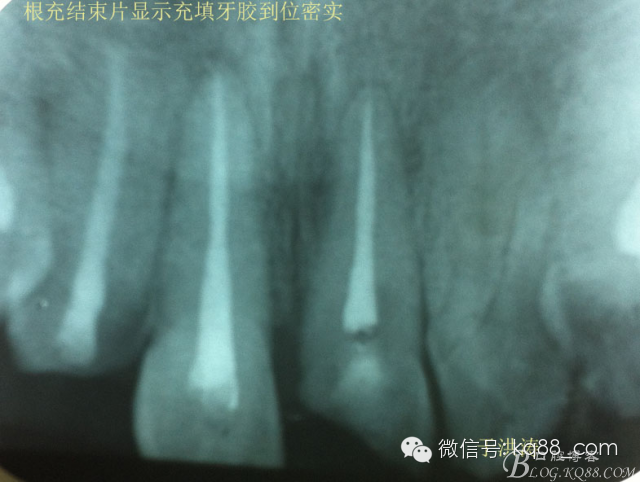

檢查:明顯可見22牙冠橫向斷裂至頸1/3處,近遠中與腭側斷裂至齦下??梢?/span>11牙冠斜向近中斷裂,近中與腭側均斷裂至齦下。21牙冠中1/3有裂痕。11 21 22松動(0),11 21叩(+),22叩(-),11 21 22探(-),11 21 22冷熱(-)。11 21 22唇側牙齦與粘膜和根尖相應部位未見明顯改變。11 22腭側牙齦增生性改變。11 21 22腭側粘膜和根尖相應部位未見改變。11 21 22舌側窩均有充填物。面部左右對稱無改變。余牙正常。(11,21,22牙冠顏色無改變)。 輔助檢查:X線片檢查11 22牙冠均有缺失。11 21 22 髓腔內均有充填物,11充填不到位, 21充填不實,22充填到位髓腔高密度影像。11 21 牙周膜有增寬,21根尖區(qū)有2mm左右低密度影像。未發(fā)現(xiàn)有牙根側穿或斷裂異物。 診斷:11,21慢性尖周炎,11,22殘冠。 治療計劃: 22無需治療。11 21 建議牙齒根管再治療。告知情況及費用。 1,11 21去除根充物。 2,11 21根管治療。 3,11 22纖維樁樹脂核修復。 4,高頻電刀去除11 22腭側牙齦組織到斷面。 5,11,21,22全瓷單冠修復牙齒。 治療過程:經(jīng)患者同意。H銼去除11 21原有充填物,未發(fā)現(xiàn)明顯滲出物,無異味。K銼疏通根管,VDW根測儀測量長度,11牙20mmWL,21牙20mmWL。S3鎳鈦器械預備根管。(全程1%次氯酸鈉沖洗EDTA溶解潤滑)試尖片顯示牙膠未到位,繼續(xù)向牙根尖各2mm進入預備。吸潮紙尖吸干根管,登士柏樹脂根充糊劑輸送至根尖部位,以測量數(shù)據(jù)用牙膠尖冷充側壓充填根管,3M玻璃離子封閉根管口。不可用患牙啃咬硬物,擇日冠修復。 輔助檢查:插針X線片顯示根管內充填物已經(jīng)取出。試尖片顯示牙膠尖未到位,繼續(xù)用K銼和機括向根尖預備。根充結束片顯示根充密實,無超充,無欠充。 醫(yī)囑:常規(guī)醫(yī)囑,不適隨診。 各步驟操作見下圖 于洪濤 2015.02.03 復 診 主訴:無疼痛,不適癥狀已經(jīng)消失。 檢查:11 21 充填物存在邊緣封閉完好,叩(-)松動(0)牙齦及周圍同初診。11 21 22無任何不適。 治療過程:由于患者自身原因即將兩個月來復診。拍X線片,去除11 22髓腔內部分牙膠,P鉆預備根管到達預定位置。粘結纖維樁,制作冠核。初預備11 21 22牙冠。高頻電刀按廠家要求功率和方法去除11 22腭側牙齦組織到達牙齒斷裂部位,調整檔位和功率繼續(xù)凝固和精修腭側組織,11 21 22排齦精修拋光。硅橡膠兩次法取模,可見模型完整肩臺清晰。制作臨時冠,科爾不含丁香油臨時冠粘結系統(tǒng)粘接。 模型送技師制作。預約義齒佩戴時間。(需術前牙齒比色) 輔助檢查:X線片顯示根尖低密度影像消失,牙周未見異常。X線片顯示纖維樁密合到位。 醫(yī)囑:不可用臨時牙肯咬硬物,不適隨診。 各步驟操作見下圖 于洪濤 2015.03.26 復 診 主訴:牙齒無癥狀,自感腭側術區(qū)舌舔粘膜不適。 檢查:臨時冠完整,無松動,邊緣緊密。牙齒無疼痛,唇側牙齦無明顯紅腫,腭側牙齦愈合良好,牙冠肩臺邊緣清晰。腭側牙齦術區(qū)中度觸及有少量滲血。 治療過程:義齒制作完成。去除臨時冠及粘結物。義齒試戴調整完全就位,無懸突,無縫隙。清洗義齒,氫氟酸處理義齒50秒(加強醫(yī)患防護),沖洗吹干,偶聯(lián)劑處理備用。基牙37%酸處理15秒,沖洗吹干,隔濕,排齦,涂第五代粘結劑。小蜜蜂雙固化樹脂水門汀激活攪拌注入義齒中,按順序就位,加壓力,牙線去除牙縫隙多余樹脂,涂阻氧劑,基牙唇腭側各光照固化3秒之后去除多余水門汀取出排齦線,繼續(xù)光照固化牙齒每個面20秒。精細查找去除多余水門汀。 醫(yī)囑:1,患牙咀嚼硬物加以注意。 2,常規(guī)醫(yī)囑,不適隨診,。 3,加強口腔衛(wèi)生意識。定期復診檢查。 各步驟操作見下圖 于洪濤 2015.04.07 回訪病例 主訴:咀嚼食物非常自如,無任何不適。 檢查:義齒牙體完整。無松動,無叩痛。唇側牙齦紅潤質韌無萎縮,腭側術區(qū)牙齦愈合良好,無炎癥改變。唇腭側根尖相應部組織無改變。余牙正常。 輔助檢查:X線片顯示牙根及周圍未見異常。未見骨萎縮。牙冠及頸部未見異常。 醫(yī)囑:定期檢查義齒,不適隨診。 各步驟操作見下圖 于洪濤2015.04.28